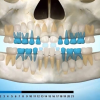

Ülemiste tsentraalsete lõikehammaste (intsisiivide) vahetumine. Retineerunud intsisiivid. Ülemised tsentraalsed esihambad lõikuvad orienteeruvalt 7-8-aastaselt. Enamasti lõikuvad samanimelised jäävhambad paaridena. Normaalne lõikumise järjekord 7, 5-aastselt: vt pilti